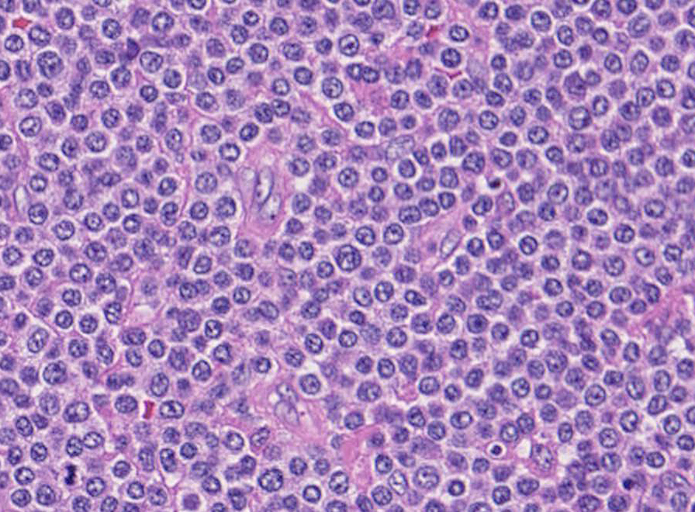

腫瘍細胞は腸管全層に密に浸潤している。粘膜表面は上皮が消失しびらんを形成。(Fig.1), 高倍率では中型, medium sized(組織球の核とほぼ同じサイズ)の類円形核をもつ比較的淡明な細胞質の異型リンパ球様細胞が密にmonotonousな増殖を示している。(Fig.2,3)

粘膜固有層には腫瘍細胞が充満し腺窩基底膜側より陰窩内に進入してIntraepithelial lymphocyte(IEL)の上皮浸潤を模倣する特徴的な蚕食像を示している。(Fig.4)

Pathological Diagnosis: Enteropathy-associated T cell lymphoma, monomorphic type

CD3ε+, CD8+, CD56-, TIA-1+, CD4-, CD5-, CD10-, CD20-, CD30-, UCHL-1-

- monomorphicな小型-中型細胞の増殖から構成される

- monotonous small round cell subtypeでは, CD8+, CD56+